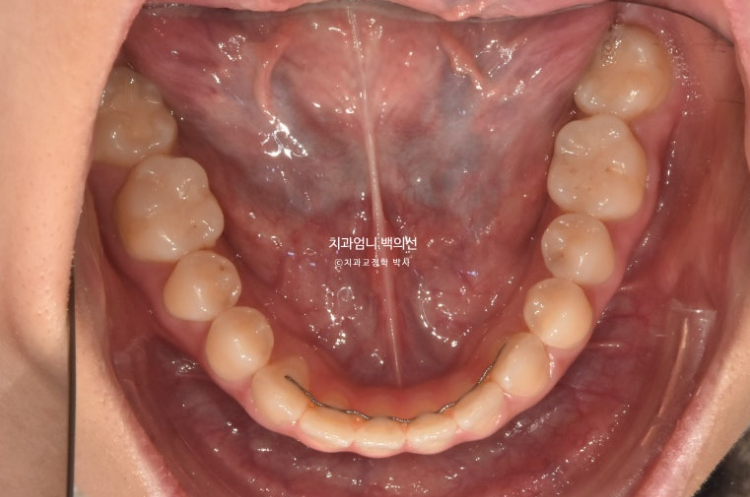

중학교때 교정을 했으나 철사유지장치가 떨어지면서 앞니가 다시 틀어진 상태입니다.

앞니 높낮이 단차와 개방교합도 보입니다.

파란 화살표 송곳니는 안쪽으로 쓰러져 있습니다.

24.12